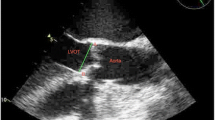

Off-line measurements and reproducibility

We analyzed the images with Philips QLab software (Philips Ultrasound, Andover, MD, USA). Using MPR, we adjusted the orthogonal imaging planes for optimal visualization of all three aortic coaptation lines (Fig. 1). By moving the red and green planes (Fig. 2), we identified the points where the cusps came together. For each one, we measured the medial and lateral coaptation heights (labelled A and B in Fig. 1) and the coaptation length (labelled C in Fig. 1). We also measured the diameter of the aortic annulus at the level of the ventricular aortic junction (VAJ) in a mid-esophageal long-axis view. All measurements were performed at the end of diastole, which we defined as the 3D frame immediately following closure of the mitral valve.

We calculated three CoapSAs for each patient: right coronary cusp/left coronary cusp, right coronary cusp/non-coronary cusp, and left coronary cusp/non-coronary cusp (Fig. 2). Since computer and silicone models have previously shown that the coaptation areas between AV cusps are trapezoidal, we calculated the CoapSA by using the following formula: trapezoid area = coaptation length × (medial coaptation height + lateral coaptation height)/2.7,8 The total CoapSA was calculated by adding all three areas for each valve. To adjust for varying valve sizes, we indexed this value to the diameter of the VAJ.